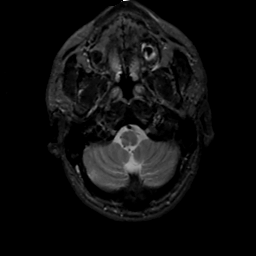

MR Study #2, February 17, 1991 -- Slice #5

[Home][Help][Clinical][Tour 1][Tour 2] Slice 5